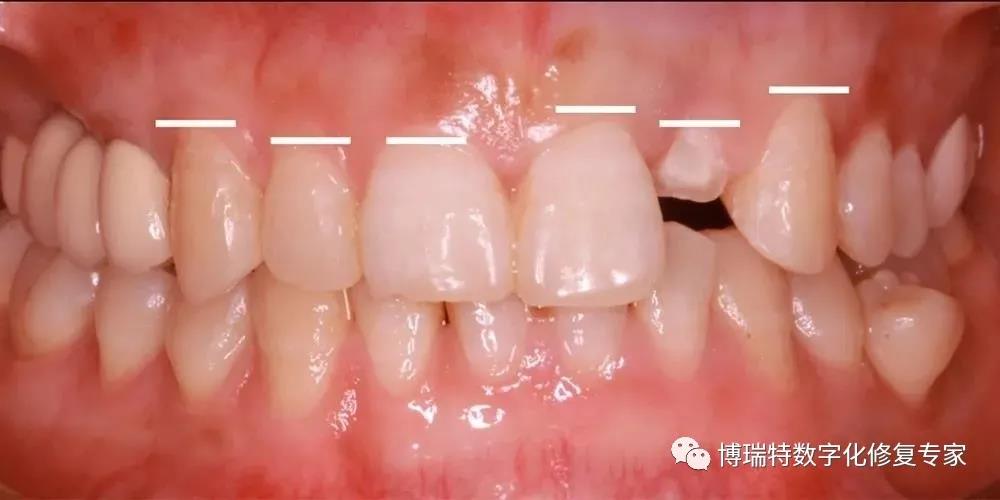

口腔检查

8226; 11、12一度松动,叩诊不适;

8226; 21牙冠三度松动,21牙冠冠向移位1.5mm,叩诊(+);

8226; 22冠根折,唇侧断面至龈下3mm,唇侧颈部凹陷;

8226; 前牙2-2中覆181015;,浅覆盖;

8226; 高位笑线,牙龈色粉,质韧,无明显红肿;

8226; 薄龈生物型,角化龈宽度充足,龈缘高度不协调;

8226; 21龈缘根向移位约1mm;